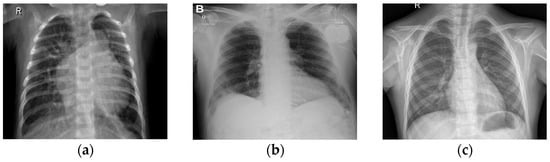

In Figure 2, it can be observed that EfficientNetB7 uses MBConv (Mobile Inverted Bottleneck Convolution) blocks with depth-wise separable convolutions, squeeze-and-excitation, and compound scaling to efficiently balance depth, width, and resolution for high-performance image classification. This figure features detailed information regarding the EfficientNetB7 architecture employed in the CXR-DNN model. The architecture is deconstructed into its fundamental layers and modules, with a particular emphasis on the advanced convolutional and MBConv blocks that improve the precision of feature extraction and classification. EfficientNetB7’s unique compound scaling and MBConv blocks with squeeze-and-excitation make it more efficient and accurate compared to other CNN models. Since Figure 1 and Figure 2 reflect varying degrees of information within the CXR-DNN model, they are linked. Presenting the whole model’s process from input to output, Figure 1 provides a macro-level perspective. Figure 2 offers a micro-level perspective, highlighting the EfficientNetB7 architecture which is fundamental for the step of feature extraction shown in Figure 1. Taken together, they offer a complete understanding of both the general framework and the complex operations of the model. Figure 1 supports the study by visually summarizing the methodology used for COVID-19 screening, making it easier for readers to grasp the end-to-end process. Figure 2 complements this by detailing the core architecture that underpins the model’s robust performance, thus emphasizing the technical innovation and depth of the proposed solution. This combination helps to clearly convey the significance of the research and its approach to achieving reliable COVID-19 diagnostics through advanced deep learning techniques. To illustrate further the differences in CXR images belonging to classes 1 (COVID-19), 2 (normal), and 3 (pneumonia), Figure 3 shows three examples of lung X-rays (one for each class).

Figure 3.

CXR images of lungs in patients: (a) healthy, (b) COVID-19, and (c) pneumonia.

Figure 3a shows a normal chest X-ray, which would reveal transparent lungs with no abnormalities. The consequence of suffering from COVID-19 is a fatal respiratory illness that causes severe breathing difficulties in both lungs (Figure 3b). The lungs may show patchy or consolidated opacities in a CXR with COVID-19 infection. When an infection strikes the lungs, it can lead to viral pneumonia (Figure 3c), which in turn leads to inflammation of the alveoli, the tiny air sacs in the lungs that are essential for exchanging oxygen and carbon dioxide, and which requires immediate medical advice or treatment. Coughing, fever, shortness of breath, chest pain, and exhaustion are all symptoms of pneumonia. Because of the inflammation, fluid may collect in the lungs, making it difficult to breathe. The best way to distinguish between COVID-19 and COVID-19 pneumonia is to consider them different steps of the same illness. COVID-19 is a respiratory sickness caused by SARS-CoV-2, and COVID Pneumonia is a complication of COVID-19 that causes the cited inflammation and fluid in the lungs [33]. There is reason for alarm with influenza, since it may lead to everything from a mild cold to pneumonia, acute respiratory distress syndrome, and even death.